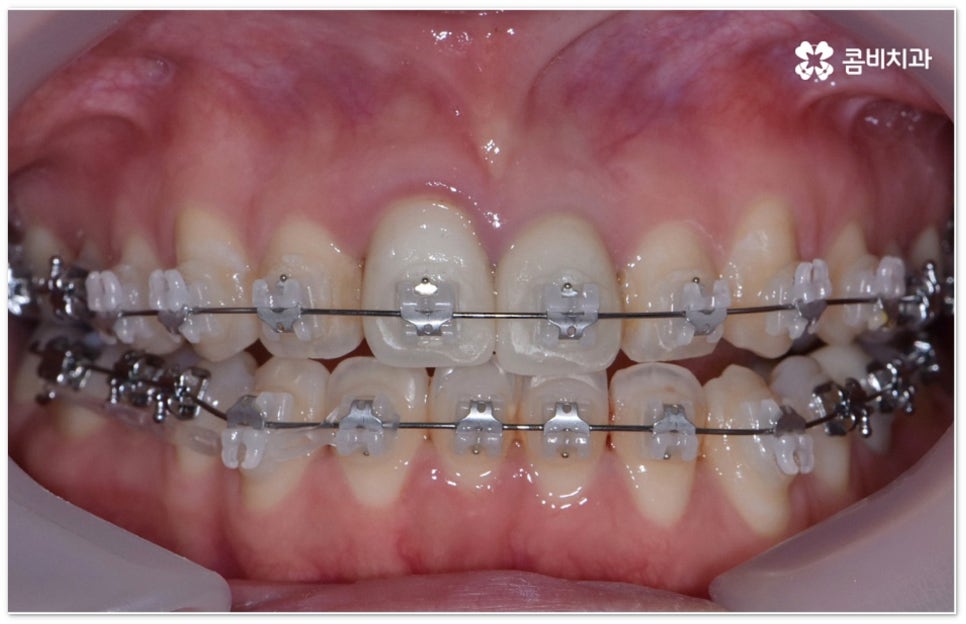

요즘 가장 많이 쓰이는 치아교정장치 인 클리피씨는 치아 색상의 세라믹 브라켓을 이용하기 때문에 심미성도 뛰어나고 자가결찰방식을 이용하여 보다 적은 힘으로 지속적이고 부드러운 치아 이동을 할 수 있도록 고안된 장치이므로 통증을 줄여줄 뿐 아니라 보통 2년 남짓 걸렸던 전체 교정 기간 역시 6개월 정도 감소시켜 줄 수 있습니다. 환자분들의 상황에 따라 내원 횟수 역시 줄일 수 있기 때문에 업무가 많이 바쁜 직장인분들의 경우에도 이용할 수 있다는 장점을 가지고 있어요.

부정교합을 개선할 때 교합이 어긋난 정도가 심하고 구조적인 원인이 커서 부분 교정이 아닌 전체 교정이 필요한 케이스인 경우라고 해도 말씀드렸던 클리피씨 교정 장치 또는 보다 심미성을 강조한 치아교정장치 들의 도움을 통해 다른 사람과 얘기를 하거나 음식을 먹을 때 브라켓이 두드러지게 드러나는 부담을 줄일 수 있으니 설측교정, 콤비교정, 투명교정, 인비절라인 등에 대해서 한 번 알아보시고 각자에게 맞는 방법으로 교정 치료를 시작해 보시길 권유드리고 있어요.